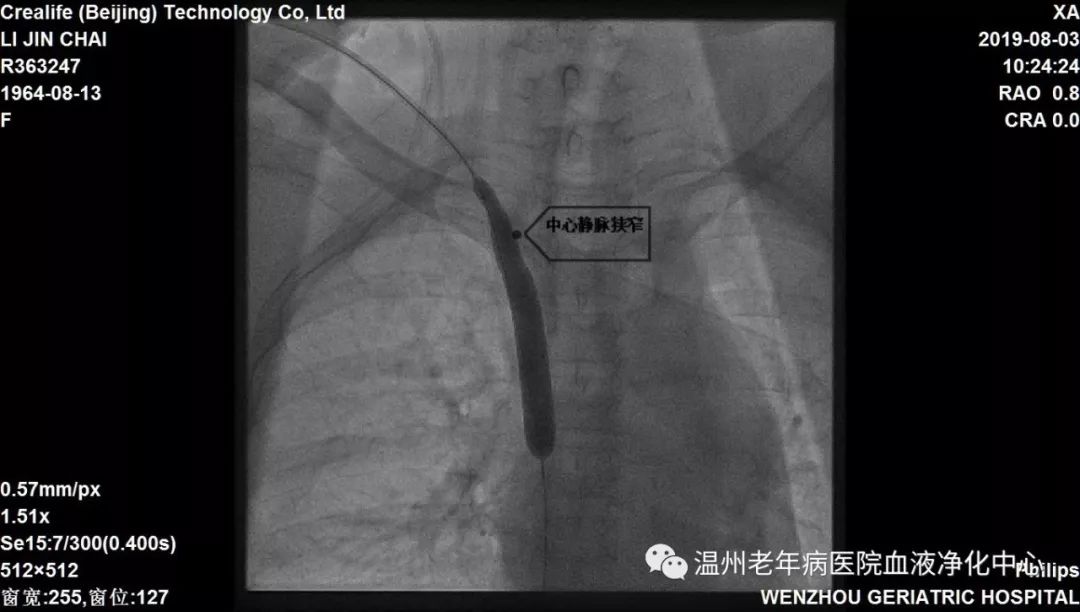

患者李某某,原发病为糖尿病肾病,罹患尿毒症13年,通路为右侧颈内静脉透析导管,患者双上肢静脉纤细,经评估不能建立自体动静脉内瘘及移植物血管内瘘,故保留导管透析已13年。近日,发现患者导管破损,出血、感染风险大,我院血液净化室主任林向东、卢寿荣医师等讨论后决定予DSA下更换导管。因患者置管时间久,考虑存在上腔静脉狭窄,常规更换导管操作可能出现拔管后无法重新置入导管,以及盲穿带来的血管破裂出血的风险,而选择DSA下能直观观察到狭窄严重程度,精确引导操作,增加手术成功率,提高手术安全性,遂决定于DSA下行中心静脉造影+球囊扩张术+更换导管术,经过大家细致操作,圆满完成手术。术毕患者导管动静脉端抽吸血流通畅,并顺利完成透析。

(中心静脉狭窄)